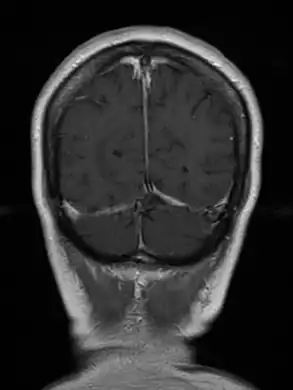

Diagnosis

Diagnosis of toxoplasmosis in humans is made by biological, serological, histological, or molecular methods, or by some combination of the above.[54] It mimics several other infectious diseases so clinical signs are non-specific and are not sufficiently characteristic for a definite diagnosis. As a result, the diagnosis is made by a trial of therapy (pyrimethamine, sulfadiazine, and folinic acid), if the drugs produce no effect clinically and no improvement on repeat imaging.[55][56]

T. gondii may also be detected in blood, amniotic fluid, or cerebrospinal fluid by using polymerase chain reaction.[57] Serological testing can detect T. gondii antibodies in blood serum, using methods including the Sabin–Feldman dye test (DT), the indirect hemagglutination assay, the indirect fluorescent antibody assay (IFA), the direct agglutination test, the latex agglutination test (LAT), the enzyme-linked immunosorbent assay (ELISA), and the immunosorbent agglutination assay test (IAAT).[54]

Even though diagnosis of toxoplasmosis heavily relies on serological detection of specific anti-Toxoplasma immunoglobulin, serological testing has limitations. For example, it may fail to detect the active phase of T. gondii infection because the specific anti-Toxoplasma IgG or IgM may not be produced until after several weeks of infection. As a result, a pregnant woman might test negative during the active phase of T. gondii infection leading to undetected and therefore untreated congenital toxoplasmosis;[63] additionally the test may not detect T. gondii infections in immunocompromised individuals because the titers of specific anti-Toxoplasma IgG may not rise.

The classic triad of congenital toxoplasmosis includes: chorioretinitis, hydrocephalus, and intracranial arteriosclerosis.[65] Other consequences include sensorineural deafness, seizures, and intellectual disability.[66]Congenital toxoplasmosis may also impact a child's hearing. Up to 30% of newborns have some degree of sensorineural hearing loss.[67] The child's communication skills may also be affected. A study published in 2010 looked at 106 patients, all of whom received toxoplasmosis treatment prior to 2.5 months. Of this group, 26.4% presented with language disorders.[68]